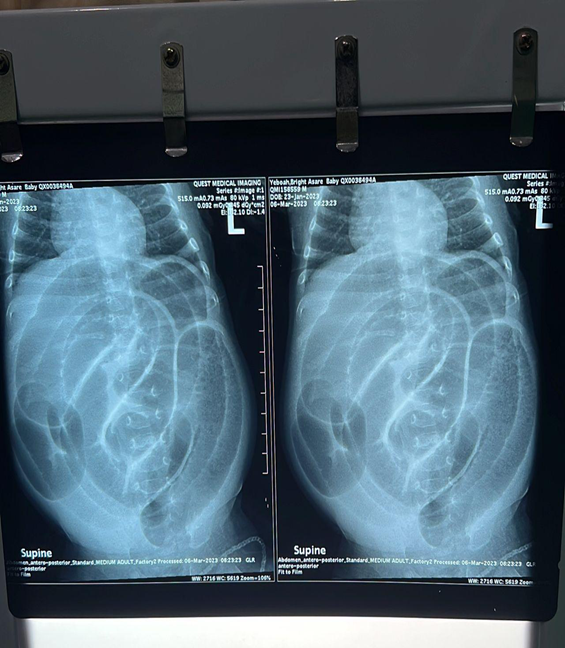

A 6 week old male was presented to hospital with a history of irritability and non-bilous vomiting for 3 days. On the 4th day, the vomiting became bilous with abdominal distension. Mother also noticed small amounts of blood in his stools. He was born by caesarian section at term on account of multiple uterine fibroids and elderly primigravida mother. His birth weight was 3.1kg. Child was fed breast milk from birth up until his presentation. On physical examination, child looked ill and was dehydrated evidenced by dried mucosa and sunken eyes. His vital signs were heart rate 140 beats per minute, respiratory rate 46 cycles per minute, temperature 37.3 degrees and oxygen saturation of 99% on room air. On abdominal examination, the patient had a grossly distended abdomen, hypertympanitic on percussion with no signs of peritoneal tenderness. On rectal examination child had mucous stools with streaks of blood in diaper. No palpable mass was found in rectum. Nasogastric tube contained bilous content which was draining copiously. Laboratory investigations showed Hb 10.4g/dL, white cell count 10.50x103, platelets 516. Blood urea and creatinine results were normal. Abdominal X-ray showed multiple dilated loops of bowel (Fig. 1). Ultrasound showed multiple distended non peristalsing loops of bowel with no target sign suggestive of intussusception. Patient was resuscitated and was taken for exploratory laparotomy which showed fibrous adhesion band in the terminal ileum about 25cm from the ileocaecal valve causing partial bowel obstruction. There was no sign of ischaemia. The portion of ileum was resected about 1cm on both ends and primary anastomosis done. Patient recovered well, tolerated full feeds and was discharged home on postoperative day five.

Fig. 1 : Plain abdominal radiograph showing dilated loops of bowel.

A plain abdominal x-ray is useful to confirm the diagnosis of intestinal obstruction it must be emphazised that the diagnosis of anomalous congenital bands is difficult to make preoperatively.